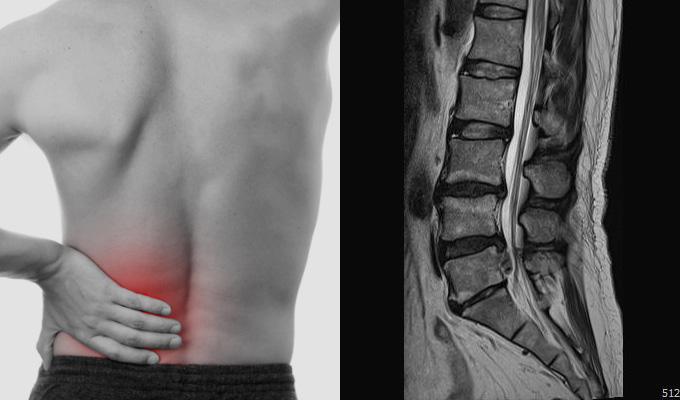

허리디스크는 척추 뼈 사이에서 충격을 흡수하는 디스크가 제자리에서 밀려나와 신경을 압박하면서 통증을 유발하는 질환을 의미합니다. 초기에는 단순 근육통처럼 뻐근하고 묵직한 느낌 정도로 시작되지만, 점차 엉덩이와 다리까지 저리고 당기는 방사통이 나타날 수 있습니다.

심한 경우 하반신 마비 또는 대소변 장애 등 심각한 상황에까지 이를 수 있어 주의가 필요한 질환이기도 합니다.